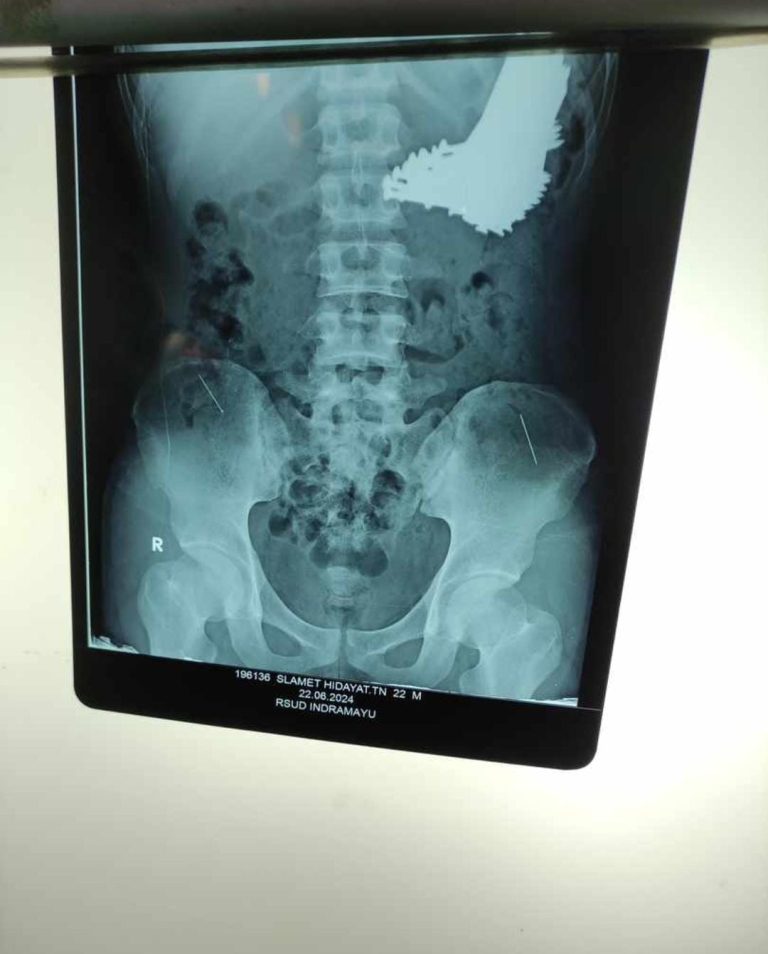

Jabar-Banten.id-Indramayu – Kejadian aneh tapi nyata, seorang Pasien yang diketahui memakan paku berhasil nyawanya...